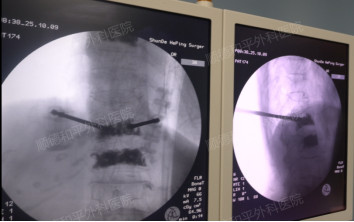

4月15日,何阿姨因“反复腰痛1个月”入院,诊断结果显示为“老年性骨质疏松伴病理性骨折”。两天后,医院为她实施了S1椎体压缩性骨折椎体成形术——通过微创手术将骨水泥注入骨折椎体,以稳定脊柱、缓解疼痛。术后摄片显示骨水泥填充成功,李奶奶的疼痛感一度减轻,便回家修养。

成形骨水泥取用

“骨水泥只是‘临时支架’,真正的康复需要患者与医生共同对抗骨质疏松。”张哉炯主任坦言,许多高龄患者误认为手术成功后就能恢复正常生活,实则骨质疏松如“隐形蛀虫”,需通过持续的抗骨质疏松治疗才能延缓骨量流失,预防再骨折。